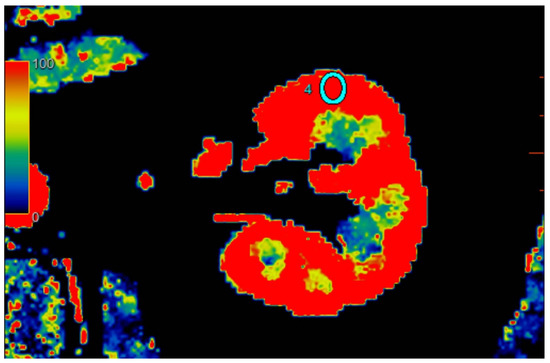

2.2.2. Quantitative Analysis of Perfusion

2.3. Kidney Ultrasound